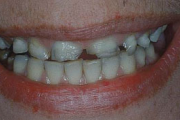

Vali sind huvitav pilt ja me näitame sellega seotud haigust ja sümptomeid